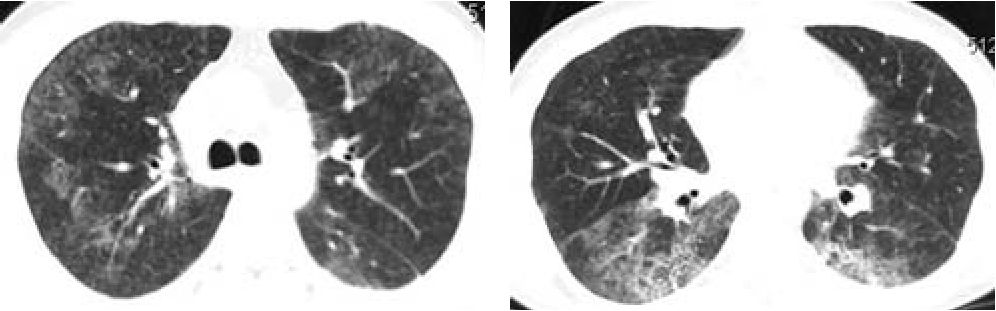

По данным компьютерной томографии органов грудной клетки (рис. 1,2), у пациента имелись признаки, характерные для текущего интерстициального поражения легких.

рис. 1, 2. Компьютерная томография органов грудной клетки.

Срез на уровне бифуркации трахеи. Определяются обширные зоны изменения прозрачности по типу "матового стекла", на фоне которых регистрируются достаточно выраженные ретикулярные изменения преимущественно в виде утолщения внутридольковых перегородок.